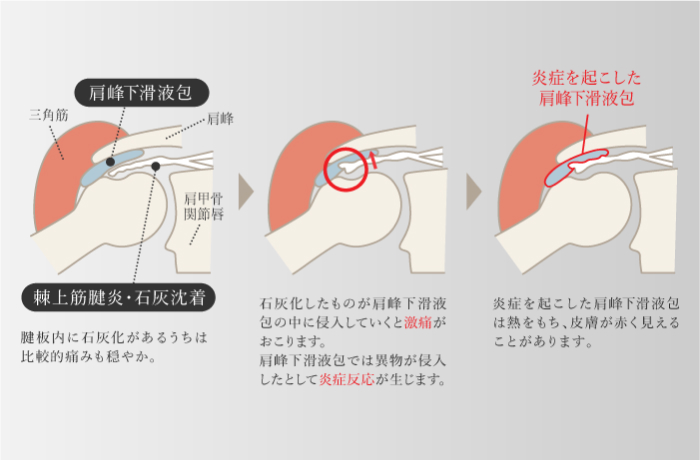

石灰沈着性腱板炎

-

肩の腱板の内部でリン酸カルシウムが結晶化して沈着し、発生する炎症。肩に痛みや運動制限などの問題が発生する。